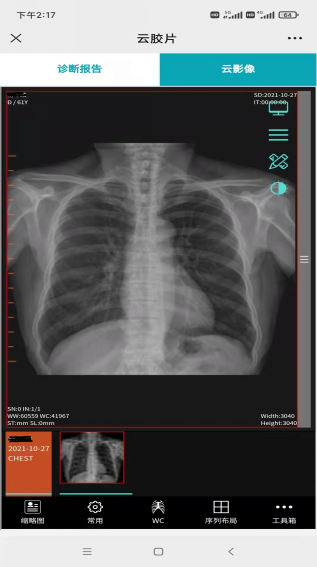

圖3 手機(jī)上查看拍片影像

“云”影像,簡單地說就是拋棄傳統(tǒng)膠片,通過手機(jī)、ipad等智能終端查看檢查報(bào)告和片子。只需微信掃一掃報(bào)告單上的二維碼,隨時(shí)隨地查閱影像和電子報(bào)告,方便攜帶和保存。如有會(huì)診需求,也可以把二維碼拍照發(fā)給相關(guān)醫(yī)師,醫(yī)師只需識別二維碼就可以查看病人的檢查結(jié)果。